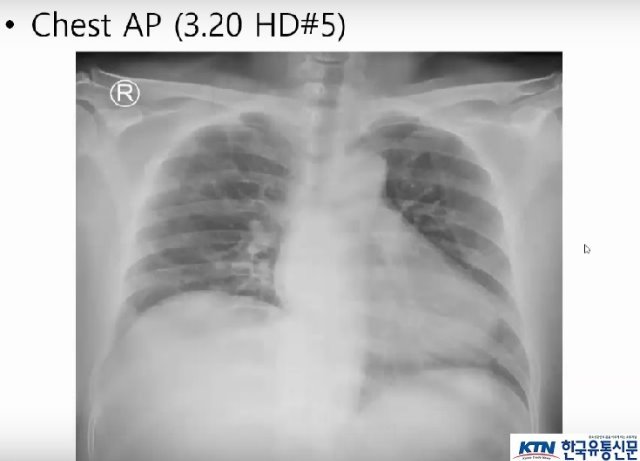

- COVID-19 중환자의 경과와 치료(조영재 분당서울대학교병원 호흡기내과)